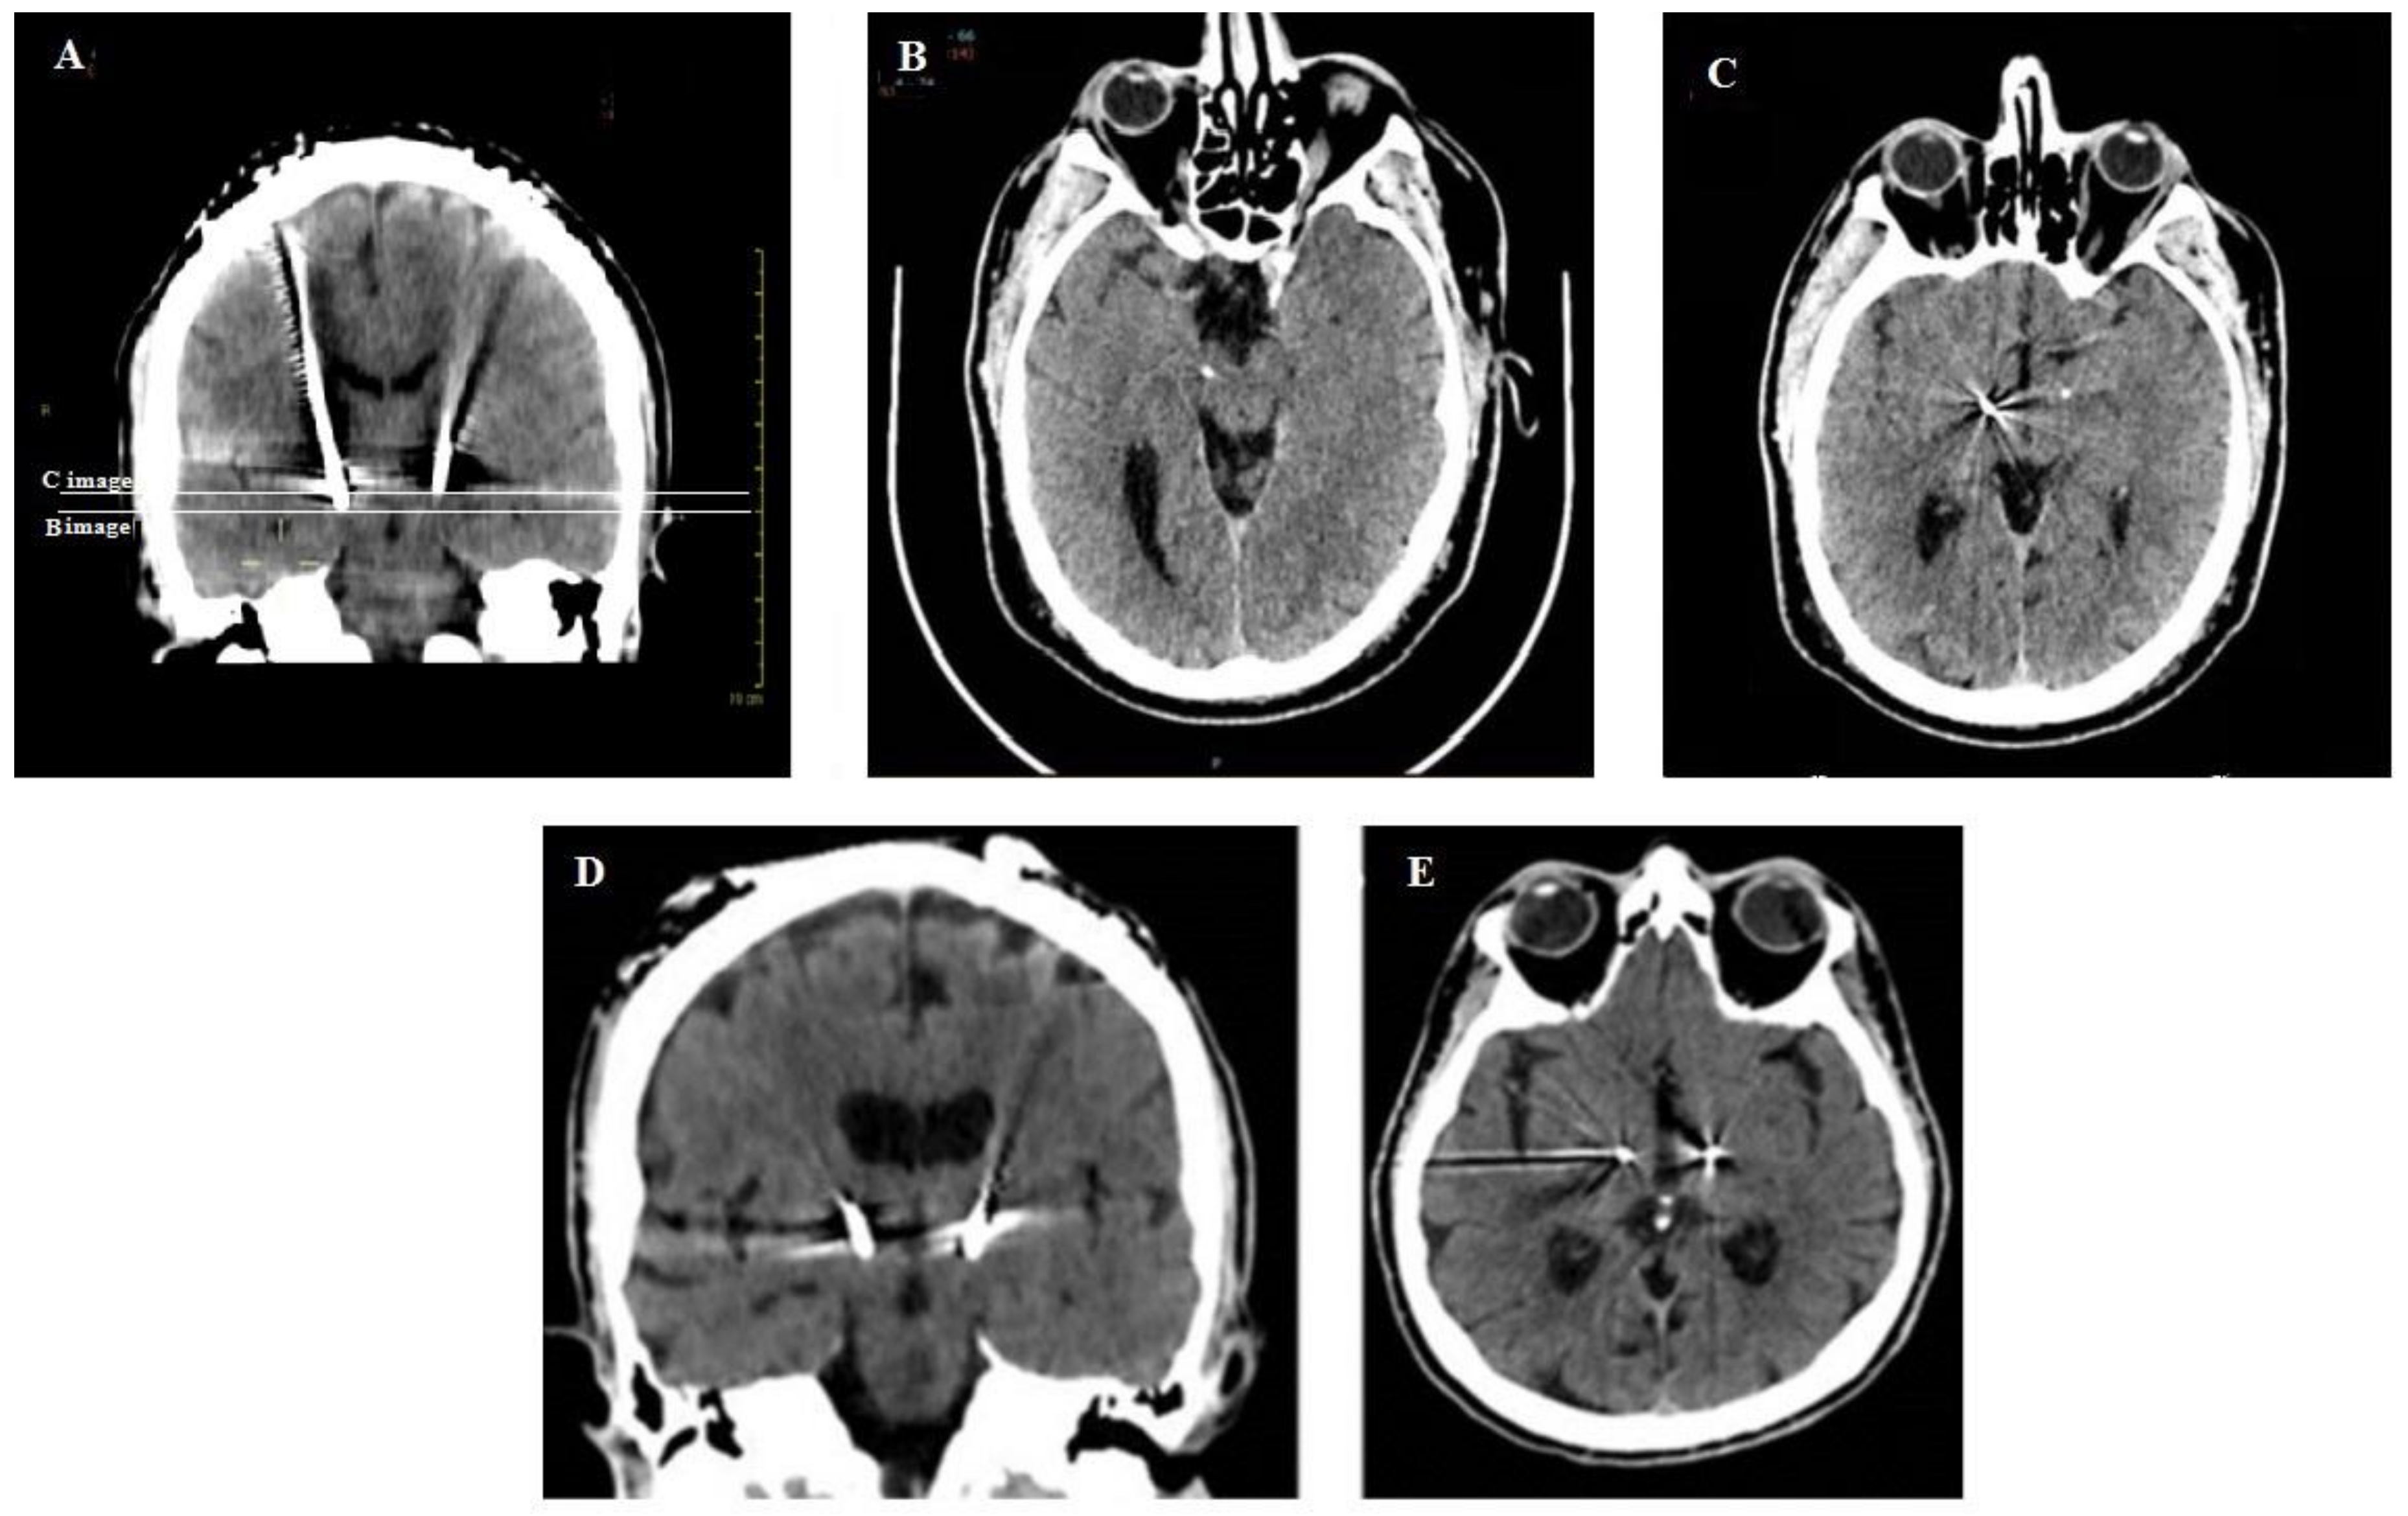

CT scans showing the depth of the electrodes in patients implanted without intraoperative X-ray control were compared with patients implanted with intraoperative X-ray control (Figure 9).

Figure 9.

A representative comparison in postoperative CT scans of a patient implanted without intraoperative X-rays control (A–C) with a patient implanted with intraoperative X-rays control (D,E). The coronal CT-scan shows the different depth of electrodes in the STN; the white lines correspond to the axial levels of the CT scan reported in B and C. The distal tips of the electrode in the right and left STN are visible in B and C, respectively. The contact 1 of the electrode in the right STN and the distal tip of the electrode in the left STN are visible in C. The correct trajectory of the two electrode and the precise correspondence of their tips in a patient implanted under X-ray control are visible in the coronal (D) and axial (E) CT scans.

The differences between the planned and actual coordinates were measured and compared in the two groups of patients. The correspondence between the planned and actual coordinates was more precise in patients implanted with the X-ray control than in patients who were postoperatively controlled by CT scan or MRI. The main differences concerned the Y and Z coordinates, where the variations were significantly greater in patients implanted without intraoperative X-ray control (Table 1).